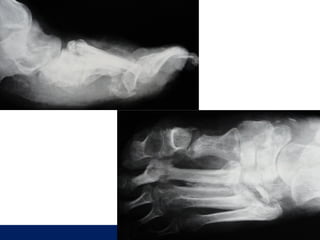

8 AY

ÖĞÜT